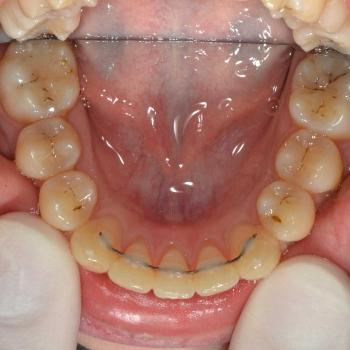

Közös döntés eredményeként fém önligírozó fogszabályozót választottunk, illetve a felső kisőrlők, illetve egy darab alsó metszőfog eltávolítására került sor. Az alsó metszőfog eltávolítása elsőre szokatlannak tűnhet, de a fogszabályozásban ez bevett gyakorlat hiszen esztétikai problémát nem okoz és a húzás által biztosított plusz hely rögtön a megfelelő helyen áll a rendelkezésünkre.

A kezelés befejeztével minden felmerülő problémát és eltérést sikerült megoldanunk, így egy funkcionálisan és esztétikailag is szép eredményt kaptunk.

A kezelés időtartama: 2 év